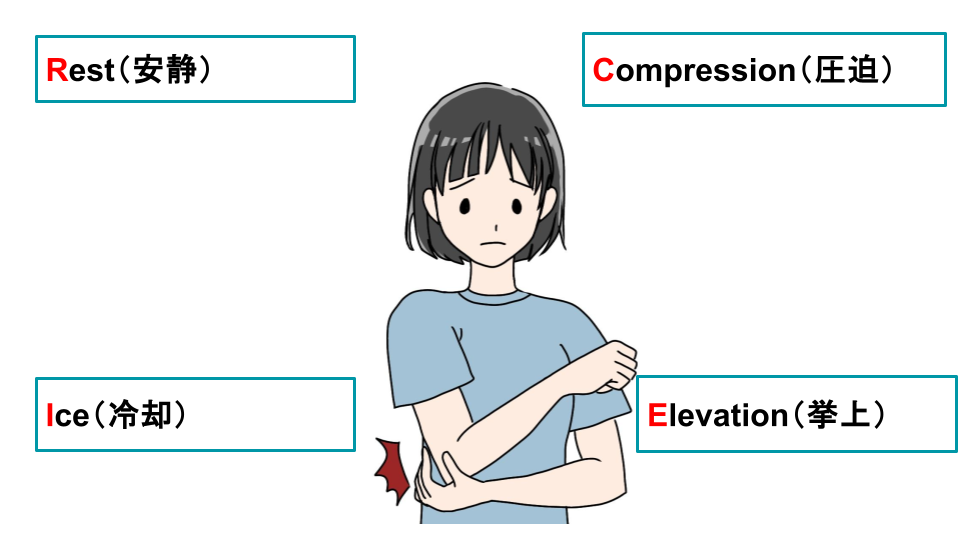

3-1.痛みが出た場合の応急処置

急に肘の外側が痛くなった場合、まずはご自身で応急処置を試してみましょう。

応急処置の基本は、RICE処置と呼ばれる方法です。

| Rest(安静) | 肘をできるだけ動かさず、安静に保つ |

|---|---|

| Ice(冷却) | 氷のうや保冷剤をタオルで包み、15〜20分程度、肘を冷やす※冷やしすぎに注意し、凍傷にならないよう気を付ける |

| Compression(圧迫) | 包帯やサポーターで肘を軽く圧迫※血行が悪くならないよう、締めすぎに注意 |

| Elevation(挙上) | 肘を心臓より高い位置に保つ※クッションや枕などを利用すると楽な姿勢を保てる |

※参考:國學院大學「捻挫の応急処置(RICE)」

RICE処置は、急性の痛みに対して一般的に行われている処置で、以下のような効果があるとされています。

炎症を抑える(冷却することで、炎症を鎮める)

痛みを和らげる(冷却と圧迫により、痛みを軽減する)

腫れを抑える(圧迫と挙上により、内出血や腫れを最小限に抑える)

応急処置で痛みが少し楽になったとしても、それは一時的なものである可能性があります。痛みがなくなったからといって、急に動かさないように注意してください。